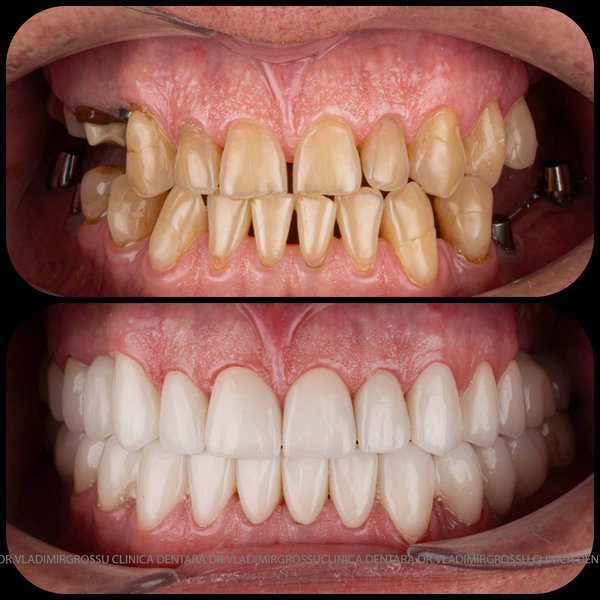

Protezarea pe implanturi dentare este soluția modernă, estetică și funcțională pentru înlocuirea dinților lipsă. Această procedură combină precizia chirurgicală cu tehnologia avansată de laborator pentru a reda pacienților zâmbetul natural, vorbirea clară și capacitatea de a mânca fără restricții.

La Clinica Dentară Dr. Grossu din Chișinău, oferim protezări pe implanturi dentare personalizate, realizate de o echipă multidisciplinară, cu ajutorul celor mai noi tehnologii digitale și materiale biocompatibile.

- Estetică superioară – imită perfect dinții naturali